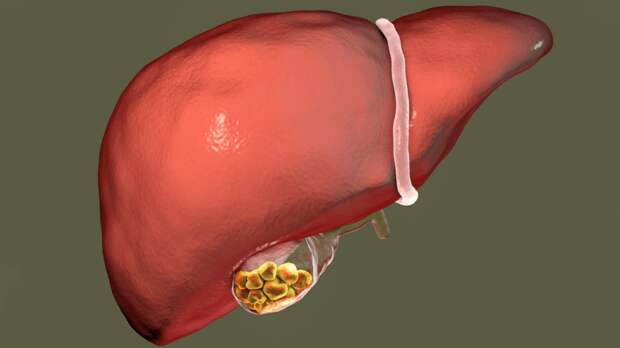

Анатомия и особенности Гартманова кармана желчного пузыря